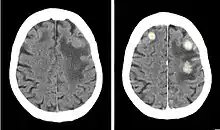

Contrast CT of a patient with brain metastases from breast cancer, before (left) and after (right) injection of iodinated contrast.